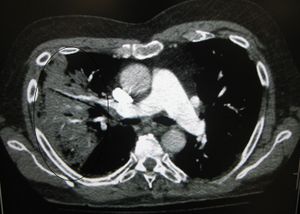

| A chest X-ray showing a very prominent wedge shaped pneumonia in the right lung. | |

AP CXR showing left lower lobe pneumonia associated with a small left sided pleural effusion